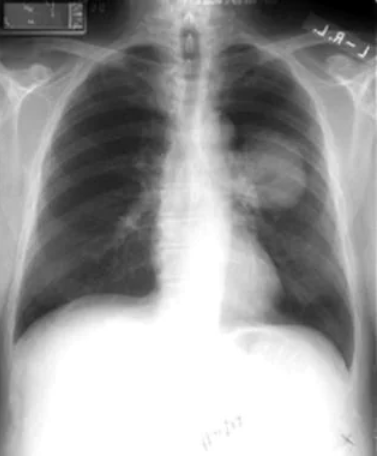

非小细胞肺癌。左上塌陷几乎总是继发于支气管内支气管癌。